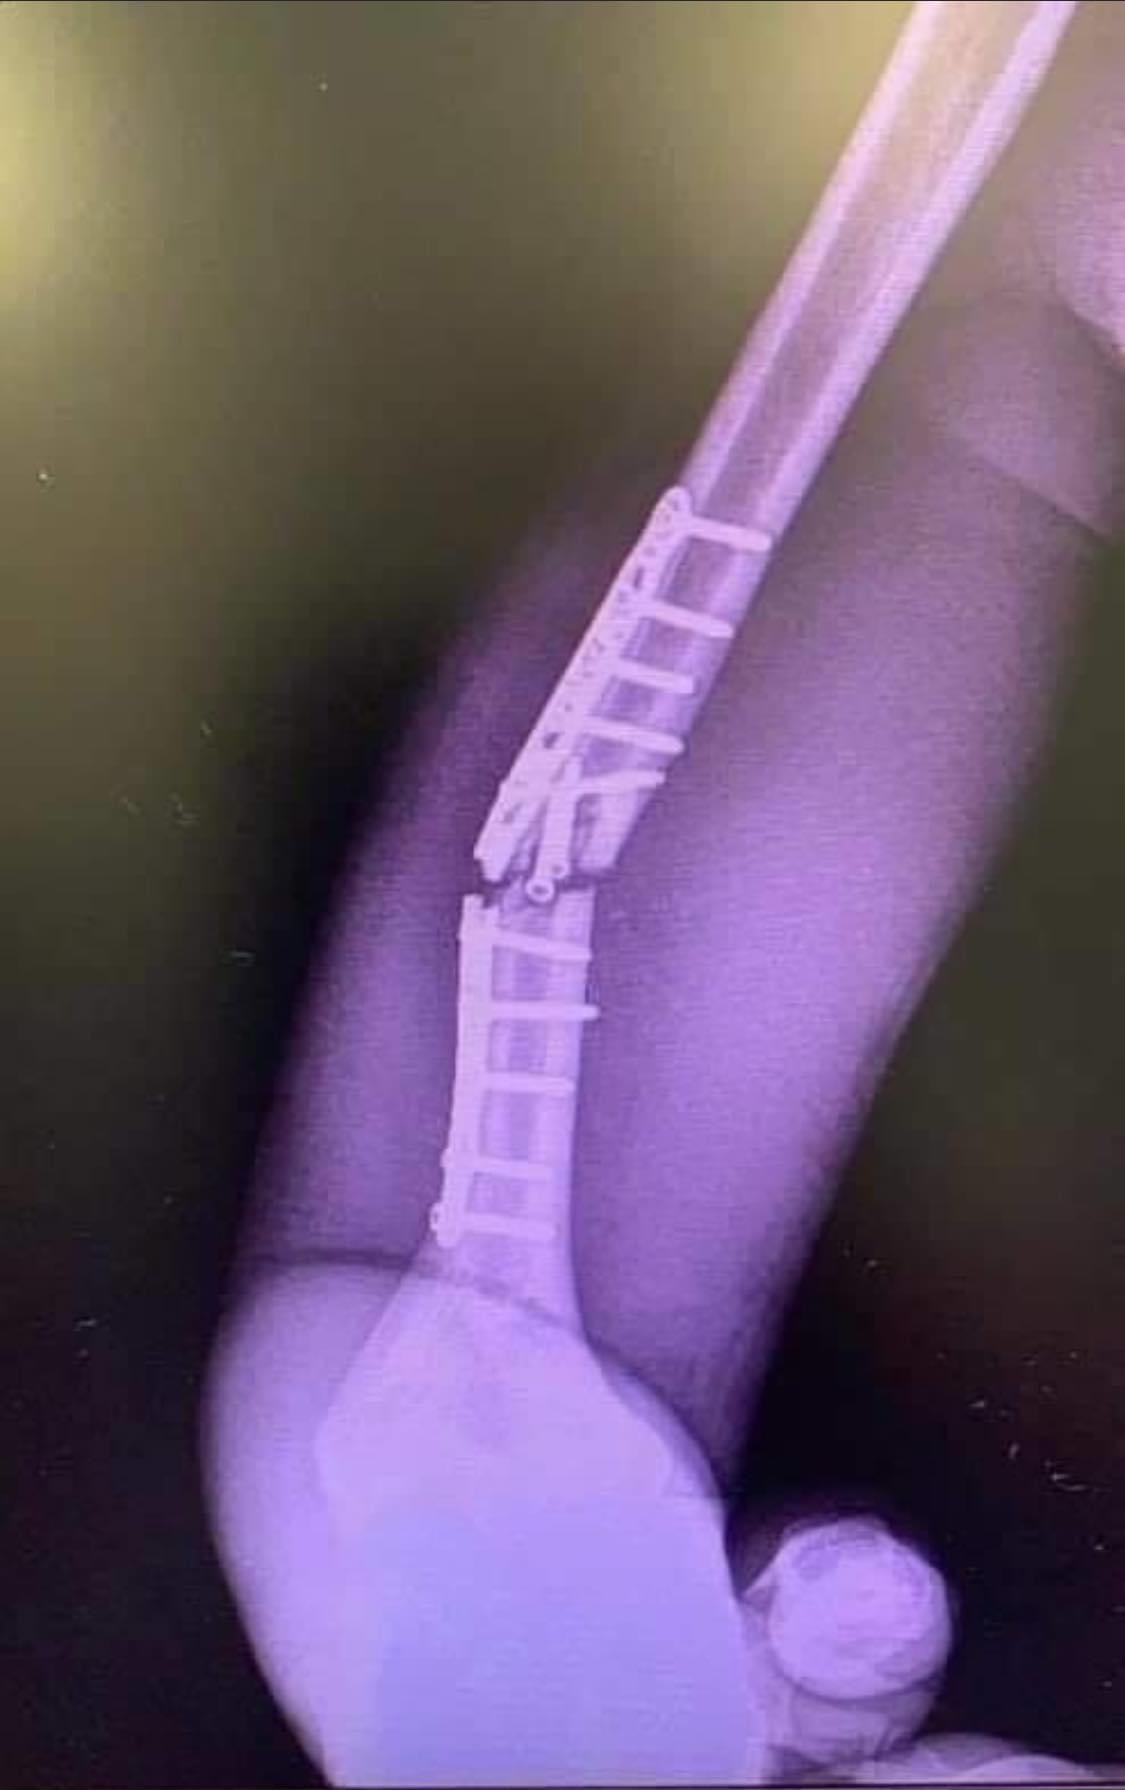

...puhhh, das Bild sieht ja mal echt übel aus.kaneun hat geschrieben:Gestern die zweite Op fuer MM93 wegen gebrochenener titan Fixur. Damit faellt er aus. Bradl ersetzt MM93.

Das ist wohl dezent untertrieben.„Der Fahrer hatte bisher keine Schmerzen. Er hat sich immer an den medizinischen Rat gehalten und auf das Gefühl seines Körpers gehört. Unglücklicherweise hat zu viel Belastung dieses Problem ausgelöst“